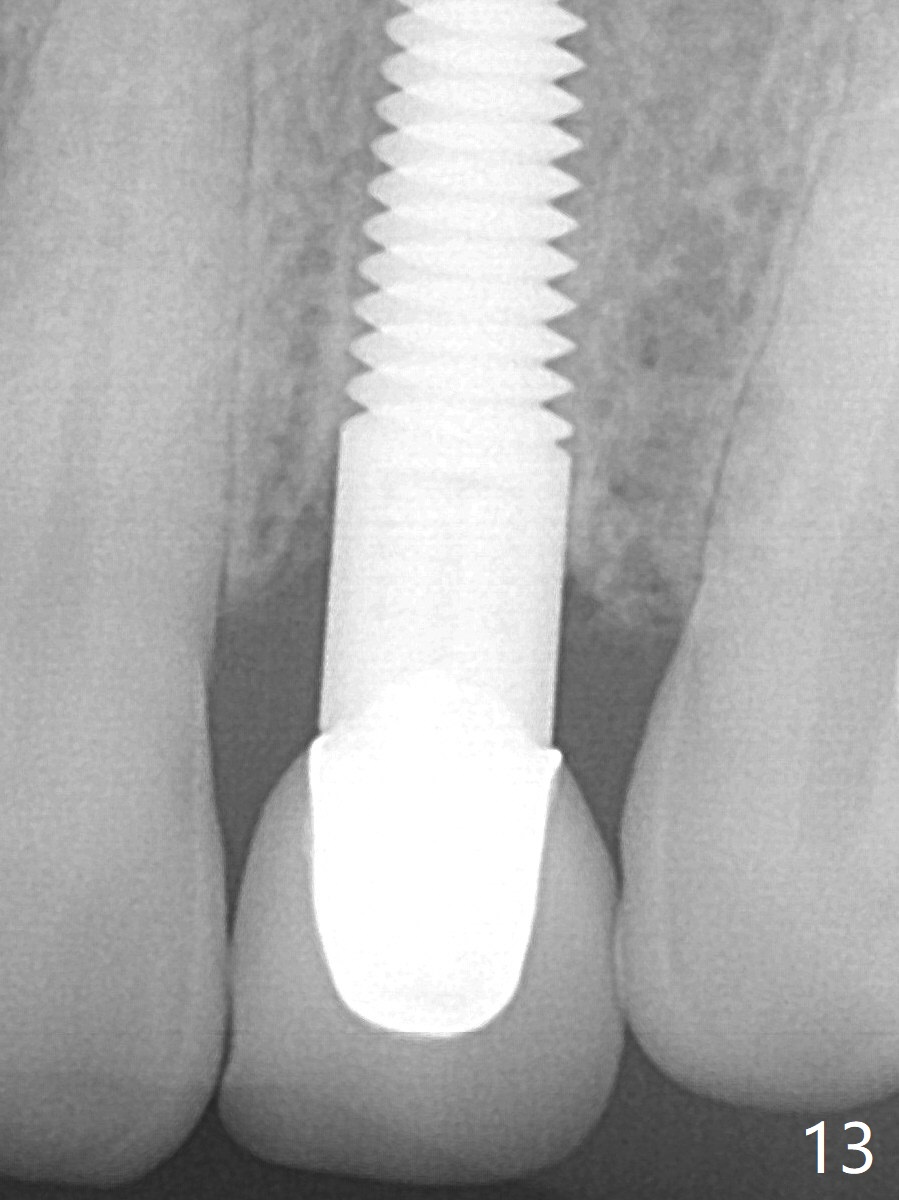

Fig.13: Three years 5 months post cementation. Dense bone forms immediately next to the implant.